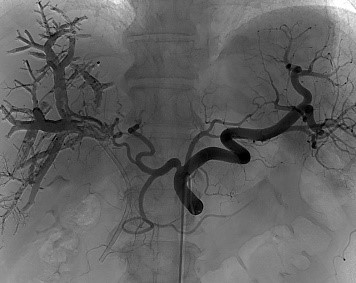

Режим Dynamic trace

Dynamic trace – режим дослідження кінцівок, передбачає рух деки столу за напрямком поширення контрастної речовини по периферичних судинах в режимі рентгенографії.